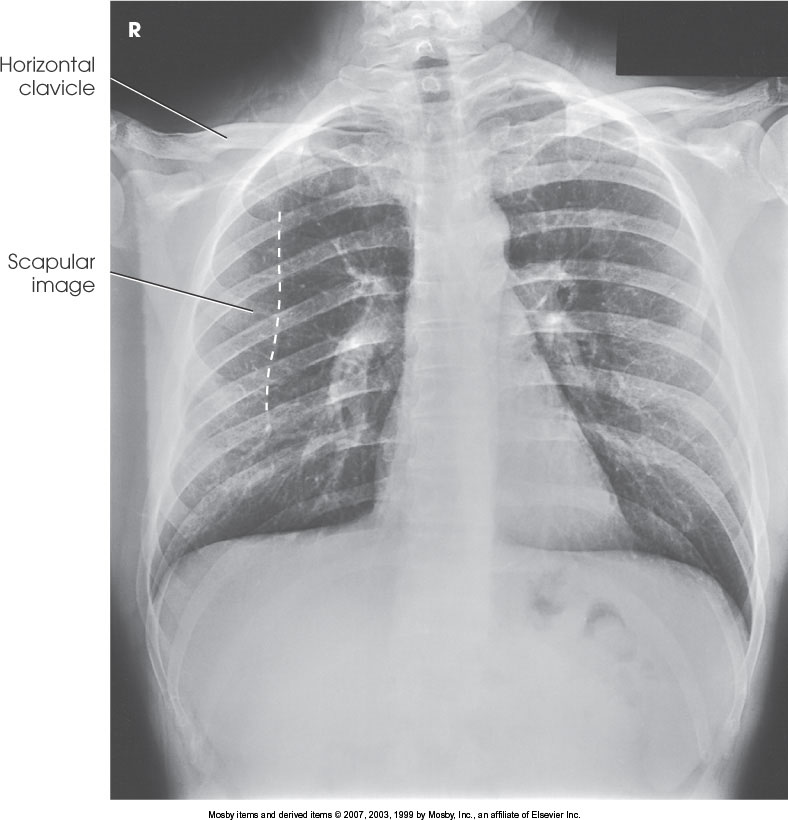

What position is demonstrated?

RAO Chest